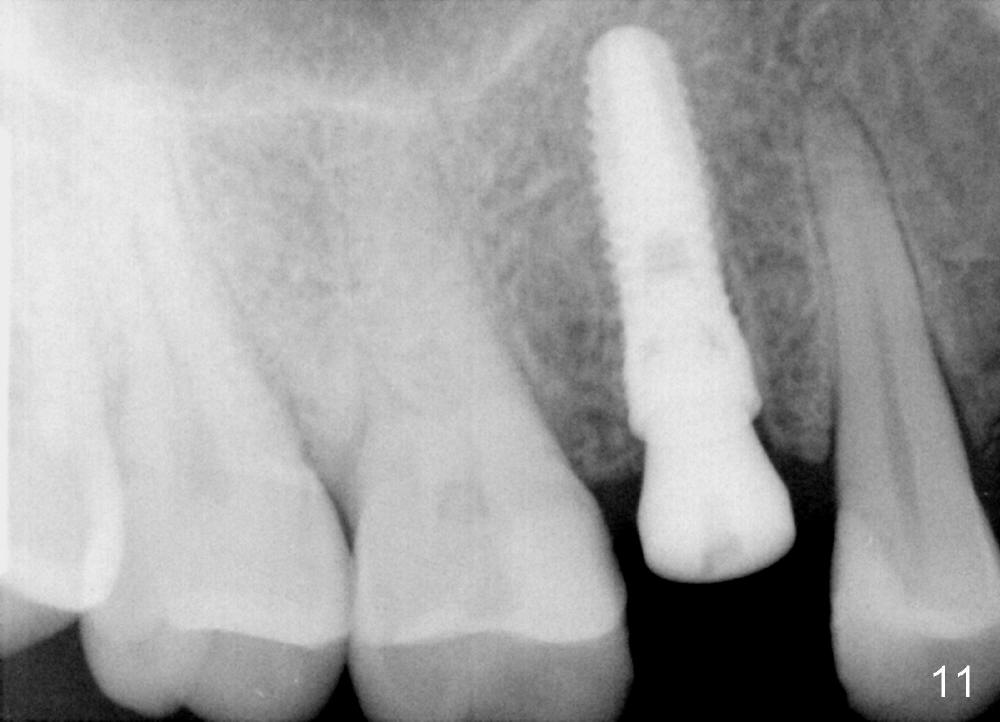

Due to insurance termination, restoration has to be done 2 months post implantation. Both the soft (Fig.10 *) and hard (Fig.11) tissues heal normally. A cemented abutment is placed (Fig.12 A). Fig.13 is taken 5 months post cementation. There is no bone resorption.